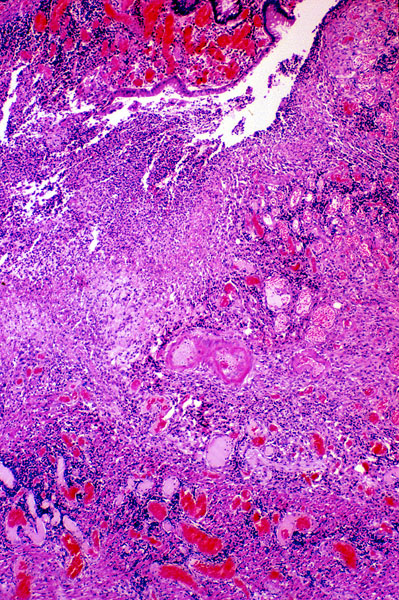

Crohn disease, histology

The surface of the large intestine is ulcerated. The underlying wall is diffusely infiltrated with chronic inflammatory cells.